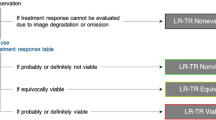

The LI-RADS treatment response categories include LR-TR nonviable, LR-TR equivocal, LR-TR viable, and LR-TR nonevaluable. A unique aspect of LI-RADS TRA is the inclusion of the category of LR-TR equivocal, which allows reporting of lesions in which the imaging appearance does not meet criteria for viable or nonviable disease. Treated tumors are characterized as equivocal when enhancement is atypical for treatment-specific enhancement pattern and not meeting criteria for probably or definitely viable tumor. In this scenario, short-term follow-up imaging is recommended, as opposed to immediate retreatment [1, 5••, 12, 13]. The LR-TR equivocal category is particularly important for tumors treated with intra-arterial and radiation-based therapies which target not only the tumor itself but also the hepatic parenchyma adjacent to the treated tumor, resulting in perfusional alterations visible on post-treatment imaging. In such instances, use of the LR-TR equivocal category helps to prevent unnecessary retreatment. While there is a risk that viable tumor is left untreated, HCC is generally a slow-growing tumor with a doubling time of 86–117 days [60,61,62], thus a wait and watch approach with a 3-month interval imaging may be a safe approach to differentiate residual viable disease from benign parenchymal perfusional alterations.

Unlike the LI-RADS diagnostic algorithm, the LI-RADS TRA currently does not use ancillary criteria for imaging assessment. However, new studies evaluating the role of ancillary features suggest increasing sensitivities to detect viable tumor. For example, one recent study [68•] evaluated LR-TRA on MRI with or without the addition of ancillary features to the existing enhancement-based criteria. Using pathologic necrosis confirmed by liver explant or surgical resection as their reference standard in 138 patients with HCC, the authors found that the use of ancillary features increased the sensitivity to detect viable disease on MRI from 76 to 84%, without sacrificing specificity (80% vs 83%). These results are comparable to a recent study by Kim et al., who found an increase in sensitivity of detecting viability from 40–67 to 83–87%, when adding the ancillary features [69]. In both studies, the ancillary features which were used included hepatobiliary phase (HBP) hypointensity, restricted diffusion, and intermediate signal intensity on T2-weighted imaging (WI). In both studies, HBP hypointensity restricted diffusion and intermediate signal intensity on T2-WI were seen in nearly all cases where the readers upgraded an LR-TR equivocal category to LR-TR viable. All three ancillary features resulted in improved sensitivities, (81%, 79%, and 83%, respectively) for detection of viability when compared to MRI alone without ancillary features (76%). Conversely, HBP isointensity was treated as an ancillary feature favoring nonviable tumor and may prove useful when arterial phase hyperenhancement is seen at the margin of an otherwise necrotic treated HCC. In these instances, isointensity on HBP may help increase a radiologist’s confidence that the observed arterial phase hyperenhancement represents perfusional abnormality and not viable tumor.

Of note, both studies revealed a marked reduction in use of the LR-TR equivocal category when incorporating ancillary features into treatment response interpretation. In Park et al., strict adherence to the LR-TR algorithm resulted in the use of LR-TR Equivocal in 9 and 12 cases out of 138 on MRI, by two readers, but incorporation of ancillary features reduced LR-TR Equivocal categorization to 2 and 0 cases, respectively [68•]. In this study, all up-categorized cases had pathologic confirmation of viable tumor [68•]. Similarly, Kim et al. [69] showed that the use of ancillary features reduced the use of the LR-TR equivocal category, from 29 and 59 assignments out of 183 cases by two radiologists, to only 2 and 14 cases, respectively. Both studies suggest improved sensitivities for detection of viable HCC when using ancillary features by correctly changing a majority of LR-TR equivocal assignments to LR-TR viable. They have also reported an excellent inter-reader agreement for LR-TR categories when using ancillary features, with a weighted kappa statistic of 0.75, which is comparable to the use of the original LR-TR algorithm [69]. These early studies support incorporation of ancillary features into the LR-TRA, as it seems to improve response assessment accuracy without apparent downside.